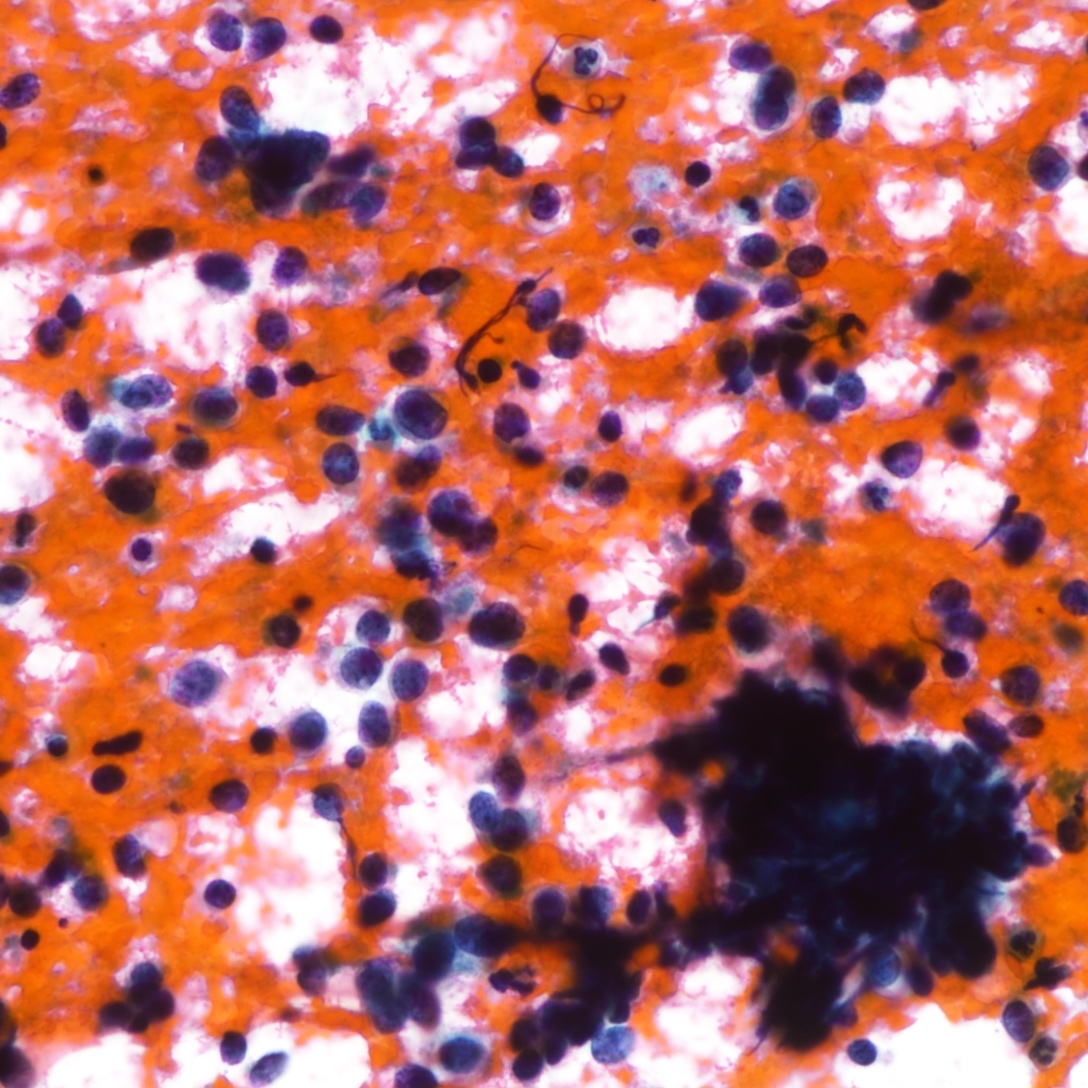

Contributed by Joshua J.X. Li, M.B.Ch.B., Gary M. Tse, M.B.B.S. and Kristen E. Muller D.O.

Small cell carcinoma

Cytology description

- Neuroendocrine features, including nuclear molding and fine salt and pepper chromatin, may be identified in small cell carcinoma

- Necrosis can be present in the background (J Cytol 2011;28:91)

- Smear preparation can accentuate crush artifact

Cytology images